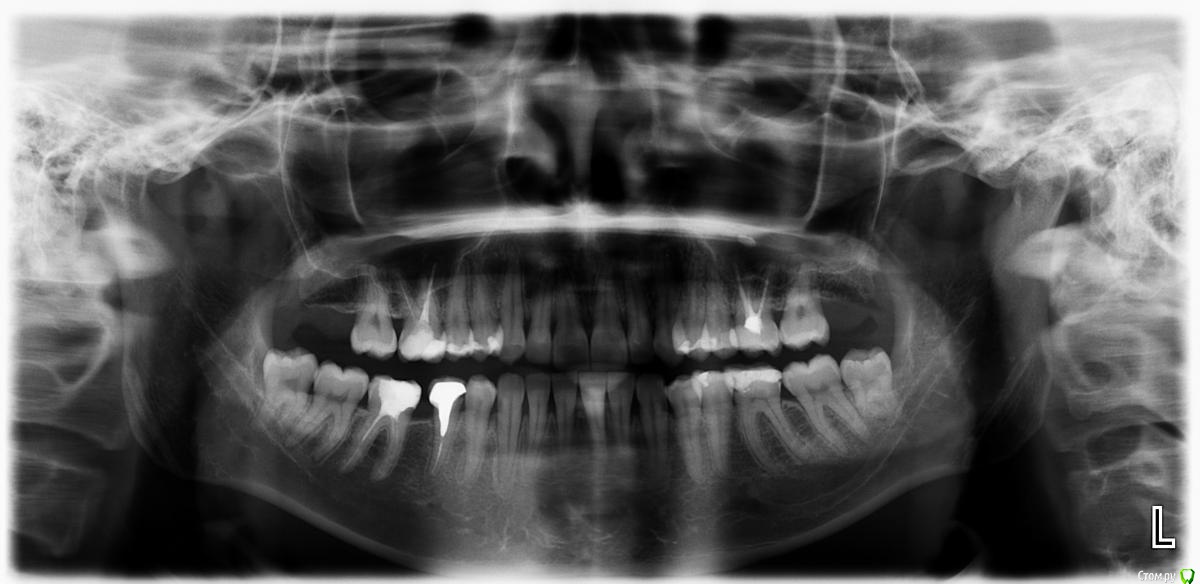

Iriss Опубликовано 24 января, 2015 Поделиться Опубликовано 24 января, 2015 Уже месяц болит зуб. В одной клинике залечили 5 и 6 слева ( на снимке справа ), боль не прошла, стало отдавать в ухо. Потом залечили маленький кариес на 5. Снова болит. Если стучат инструментами по зубам, боли нет. Реагирует на холодное, горячее и еду. Так же , когда чищу между 5 и 6 зубной нитью, неприятные ощущения, когда нить выходит вниз.Сделали еще снимок ( прилагается ), третий врач ничего не заметил, кроме белого пятна на снимке в десне , над 5 и 6 зубом. Отправил к Лору. До этого у Лора была , то же ничего не заметил. Что это и может ли из за этого болеть зуб? Спасибо. Ссылка на комментарий

red_butler Опубликовано 24 января, 2015 Поделиться Опубликовано 24 января, 2015 я бы уделил пристальное внимание зубу 3.6 (жевательный на нижней челюсти слева) 3 Ссылка на комментарий

Iriss Опубликовано 24 января, 2015 Автор Поделиться Опубликовано 24 января, 2015 я бы уделил пристальное внимание зубу 3.6 (жевательный на нижней челюсти слева)Там вроде бы не болит. Мне четко кажется что боль сверху . И что такое наверху на снимке справа( на десне ) , врач сказал забытый материал? Это не может болеть? Ссылка на комментарий

red_butler Опубликовано 24 января, 2015 Поделиться Опубликовано 24 января, 2015 Те пятно на снимке не может быть причиной боли? это пломбировочный материал и должен в первую очередь заботить ЛОРа, хорошо бы сделать Кт верхнечелюстного синуса.Но это к вашим жалобам отношения не имеет Ссылка на комментарий

shishok Опубликовано 24 января, 2015 Поделиться Опубликовано 24 января, 2015 А мне не нравится 38:ощущение,что на задней поверхности глубокая полость.Его бы проверить. 1 Ссылка на комментарий

shishok Опубликовано 24 января, 2015 Поделиться Опубликовано 24 января, 2015 скажите плиз, что такое 38?Зуб мудрости внизу слева. Ссылка на комментарий

shishok Опубликовано 25 января, 2015 Поделиться Опубликовано 25 января, 2015 А пятно на снимке не может быть причиной боли? Это не киста?Пятно на снимке -возможная скрытая кариозная полость(может быть причиной боли).Это не киста(киста расположена на верхушках корней). Ссылка на комментарий